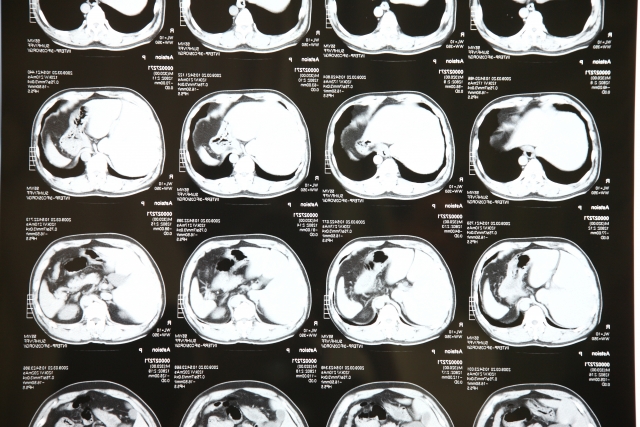

CT検査は、体の周りを360度回転しながら連続的にレントゲンを照射し、断面図を合成する技術です。

情報量が圧倒的に多いため、1回の検査でレントゲン数十回〜100回分以上の放射線を使用します。

しかし、その分、レントゲンでは見つけられない数ミリ単位のがんや出血を発見できるという、

命に直結するメリットがあります。